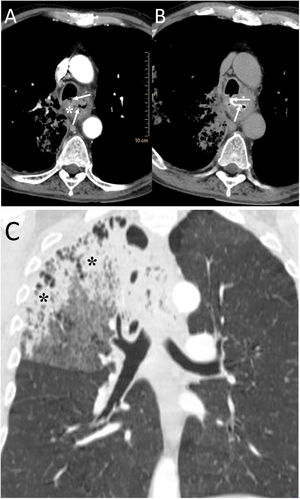

A 58-year-old man with fever and dysphagia. A and B) The computed tomography showed an oesophageal wall thickening (white asterisk) and a fistulous path between the oesophagus and the intrathoracic trachea, clearly visualised when oral contrast was administered (white arrows). C) In the pulmonary parenchyma window, pulmonary consolidation was visualised in the right upper lobe (black asterisks). The radiological findings indicated an oesophageal neoplasm with tracheo-oesophageal fistula and aspiration pneumonia in the right lung. The patient was treated by placing an oesophageal endoprosthesis, with significant clinical improvement.

A 48-year-old man with lung neoplasia treated with surgery and chemotherapy. A and B) The computed tomography (CT) scan showed the presence of a subcarinal adenopathy (black asterisk) that in the next control CT scan necrotised and filled with air (white asterisk). In addition, a right lower lobe lung consolidation was seen due to aspiration pneumonia (white asterisks). C) MinIP reconstruction (coronal plane) revealed a fistula between the intermediate bronchus (black arrow) and the necrotic adenopathy (white arrows).